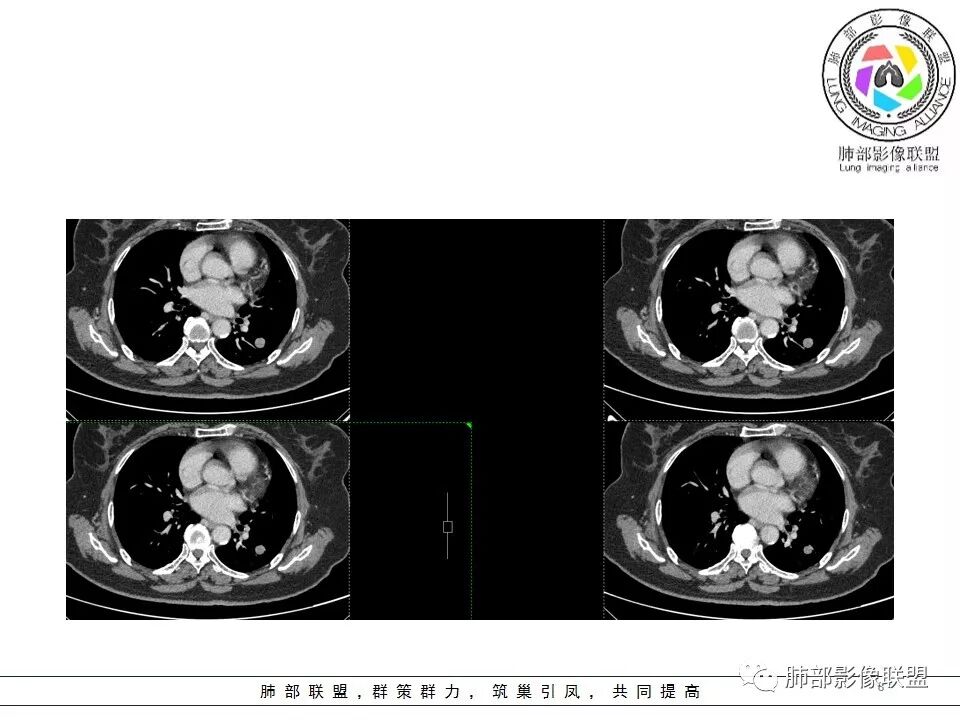

南边分析

南边 :

血管贴边征一般是有前提的

孤立结节,类圆形,边缘光滑,周围干净

与支气管有关吗?好像显示不明显

与血管的关系?

局部稍推压变

对比同级别血管稍增粗

密度尚均匀

CT值46H

增强67HU

动脉期弱一些,后期强化明显一些

动脉期边缘斑点状、结节状强化为主

后期趋向于均匀强化

动脉期测量区域——中央,不是强化区域

其实强化还算是中度,幅度超过20HU

支持良性

PSP可能 错构瘤待排